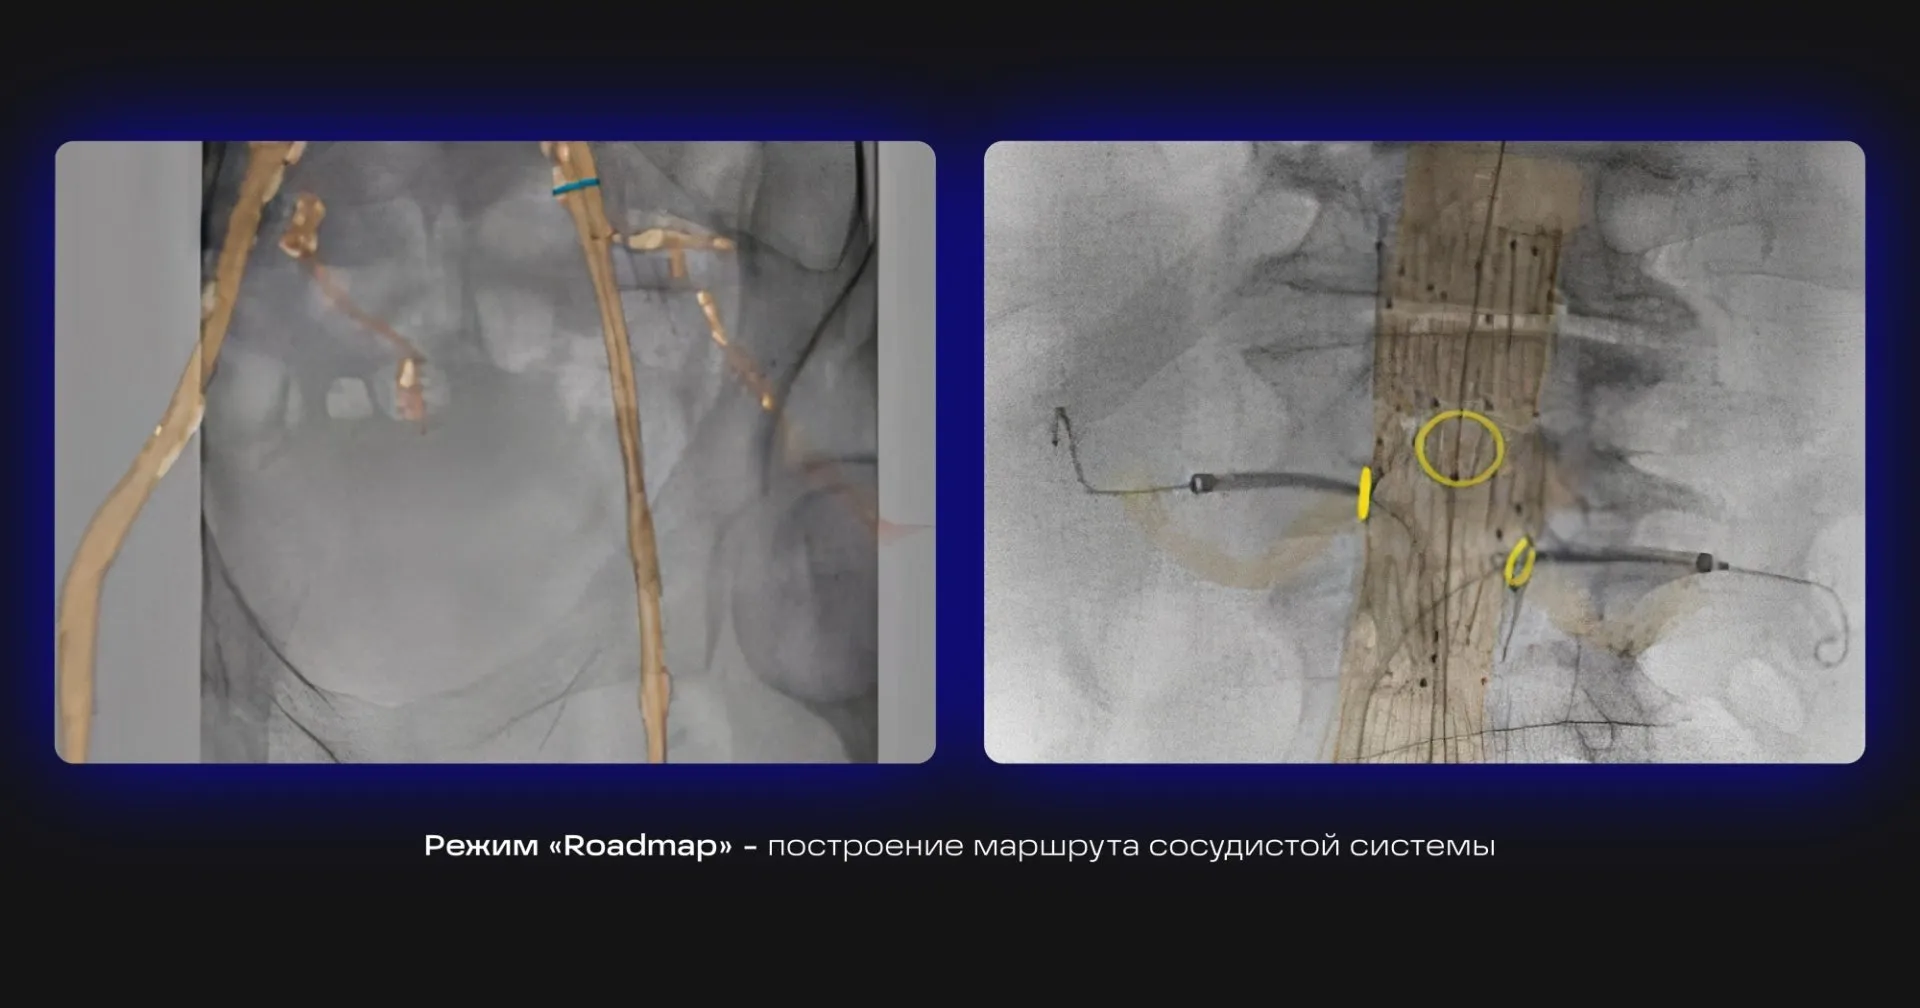

Режим «Roadmap» — построение маршрута сосудистой системы на «живом» изображении в реальном времени для навигации проводника.

Для работы С-дуги в этих режимах потребуется наличие автоматического инжектора (инъектора) для ангиографических исследований сердца и сосудов.